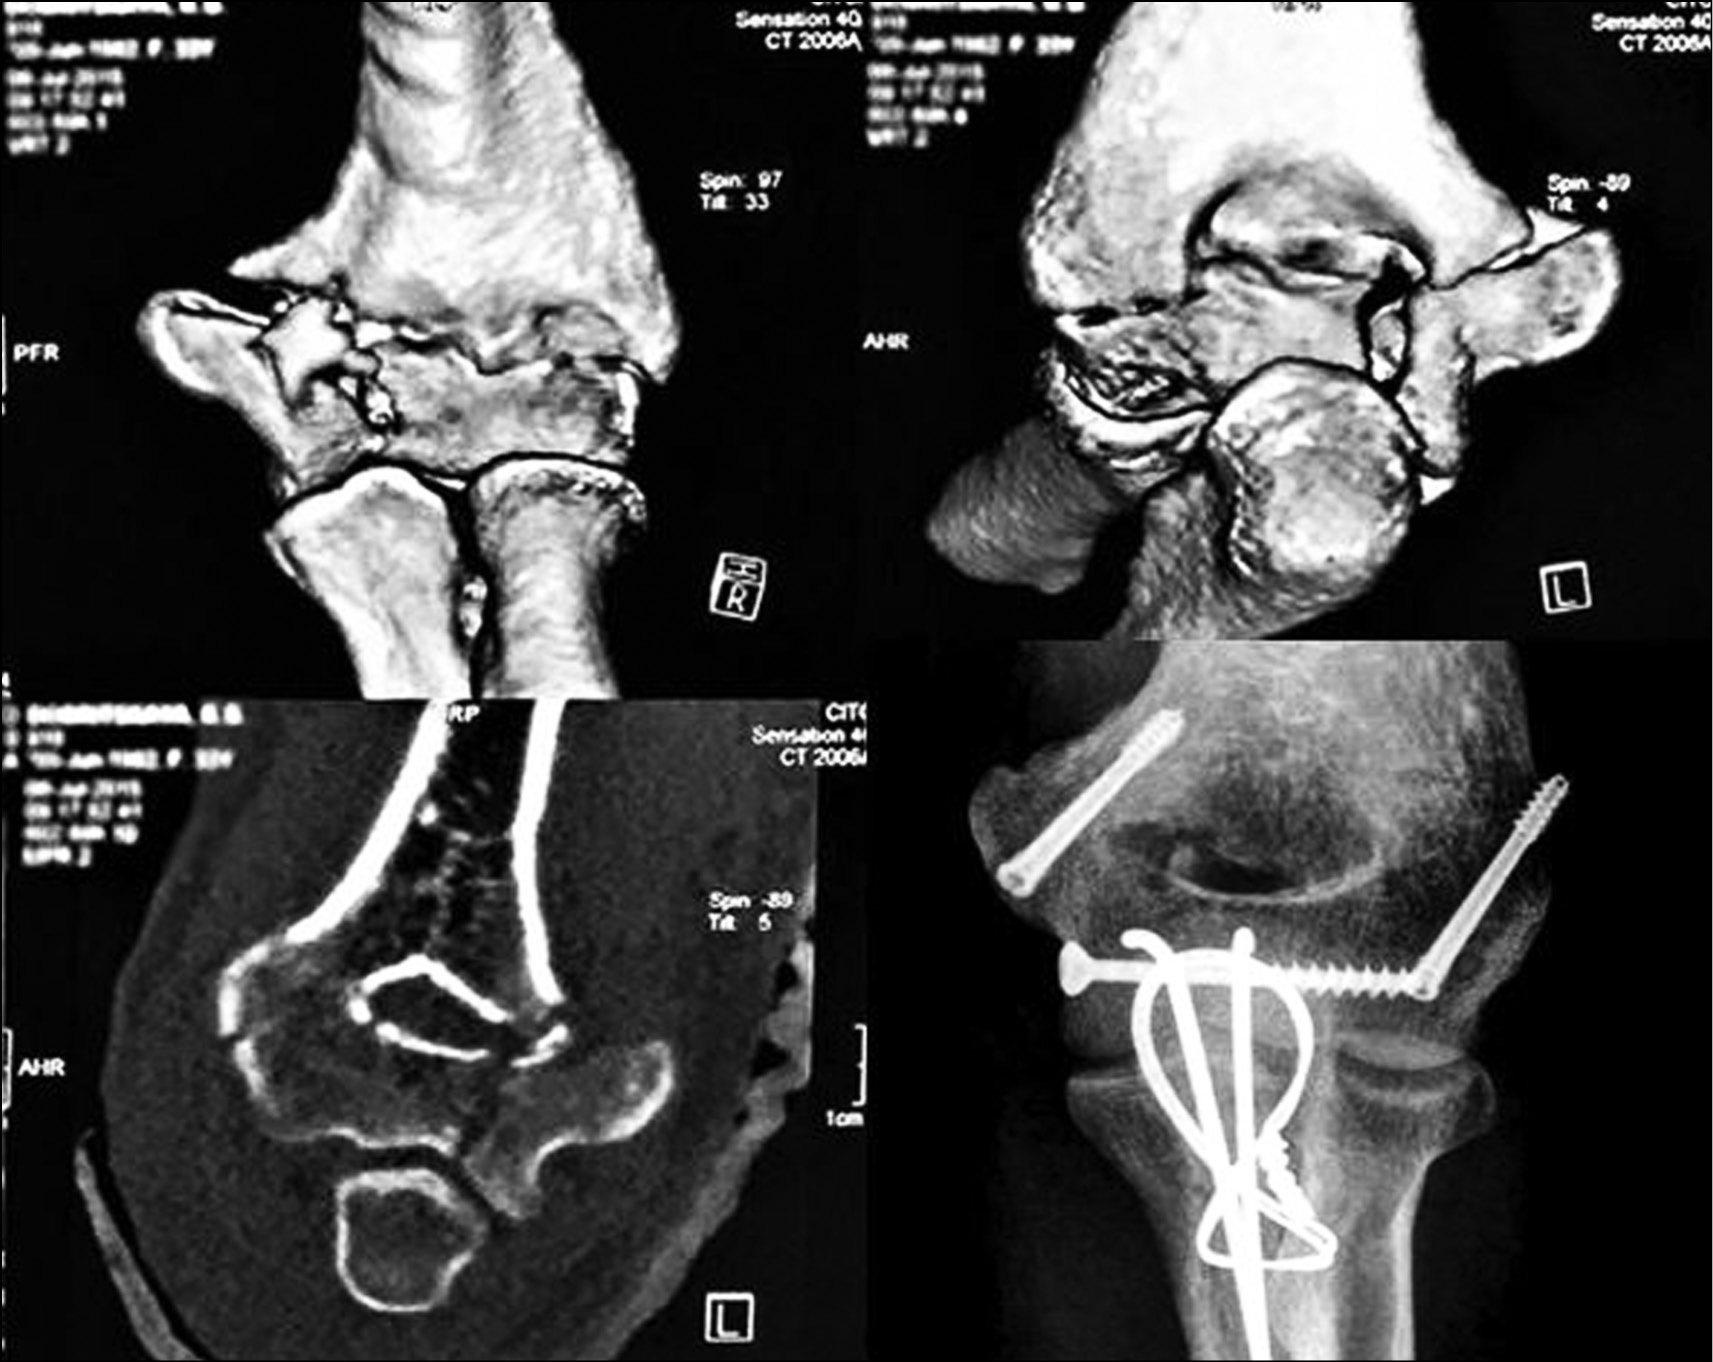

Клинический пример № 1. Пациент, 20 лет, травма за 10 мес до поступления в результате дорожно-транспортного происшествия. Проводилось лечение по месту жительства в гипсовой лонгете сроком 4 нед. После снятия лонгеты назначен курс лечебной физкультуры, однако после 8 мес объем движений в локтевом суставе неудовлетворительный из-за неправильно сросшегося перелома блока и головочки мыщелка плечевой кости (рис. 3, а–b). Выполнен открытый артролиз левого локтевого сустава с моделирующей резекций блока мыщелка и головки лучевой кости. Через 6 сут после первой операции ввиду недостаточного объема пассивных движений на фоне адекватного обезболивания, закрыто наложен ШДА (рис. 3, c). На 3-и сутки начаты пассивные движения в локтевом суставе с помощью сгибающей-разгибающей штанги, через 4 нед. начаты активные движения в ШДА. Срок фиксации в аппарате — 7 нед. В дальнейшем назначен курс реабилитационного лечения. Больной осмотрен через 1 год после операции, объем движений в локтевом суставе удовлетворительный (рис. 3, d).

Рис. 3. Пациент, 20 лет: а — объем движений в локтевом суставе при поступлении; b — компьютерная томография при поступлении; c — открытый артролиз локтевого сустава с наложением шарнирно-дистракционного аппарата Оганесяна; d — результат лечения через 1 год после операции

Fig. 3. Patient, 20 years old: a — range of motion in the elbow joint upon admission; b — computed tomography at admission; c — open arthrolysis of the elbow joint with the imposition of Oganesyan’s hinge-distraction apparatus; d — the result of treatment 1 year after surgery